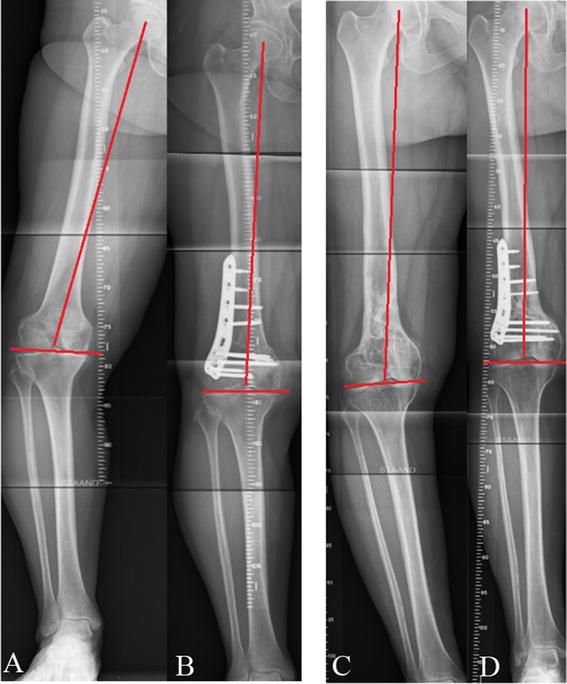

Bow legs, also known as genu varum, is a condition where the legs appear bowed outwards when standing. This condition can cause discomfort, pain, and even difficulty walking. In severe cases, surgery may be required to correct the alignment of the legs. In this article, we will discuss the causes, symptoms, and treatment options for bow legs, including the various surgical procedures available.

A doctor can diagnose bow legs by performing a physical examination and assessing the alignment of the legs. Imaging tests such as X-rays or MRI scans may also be used to confirm the diagnosis.